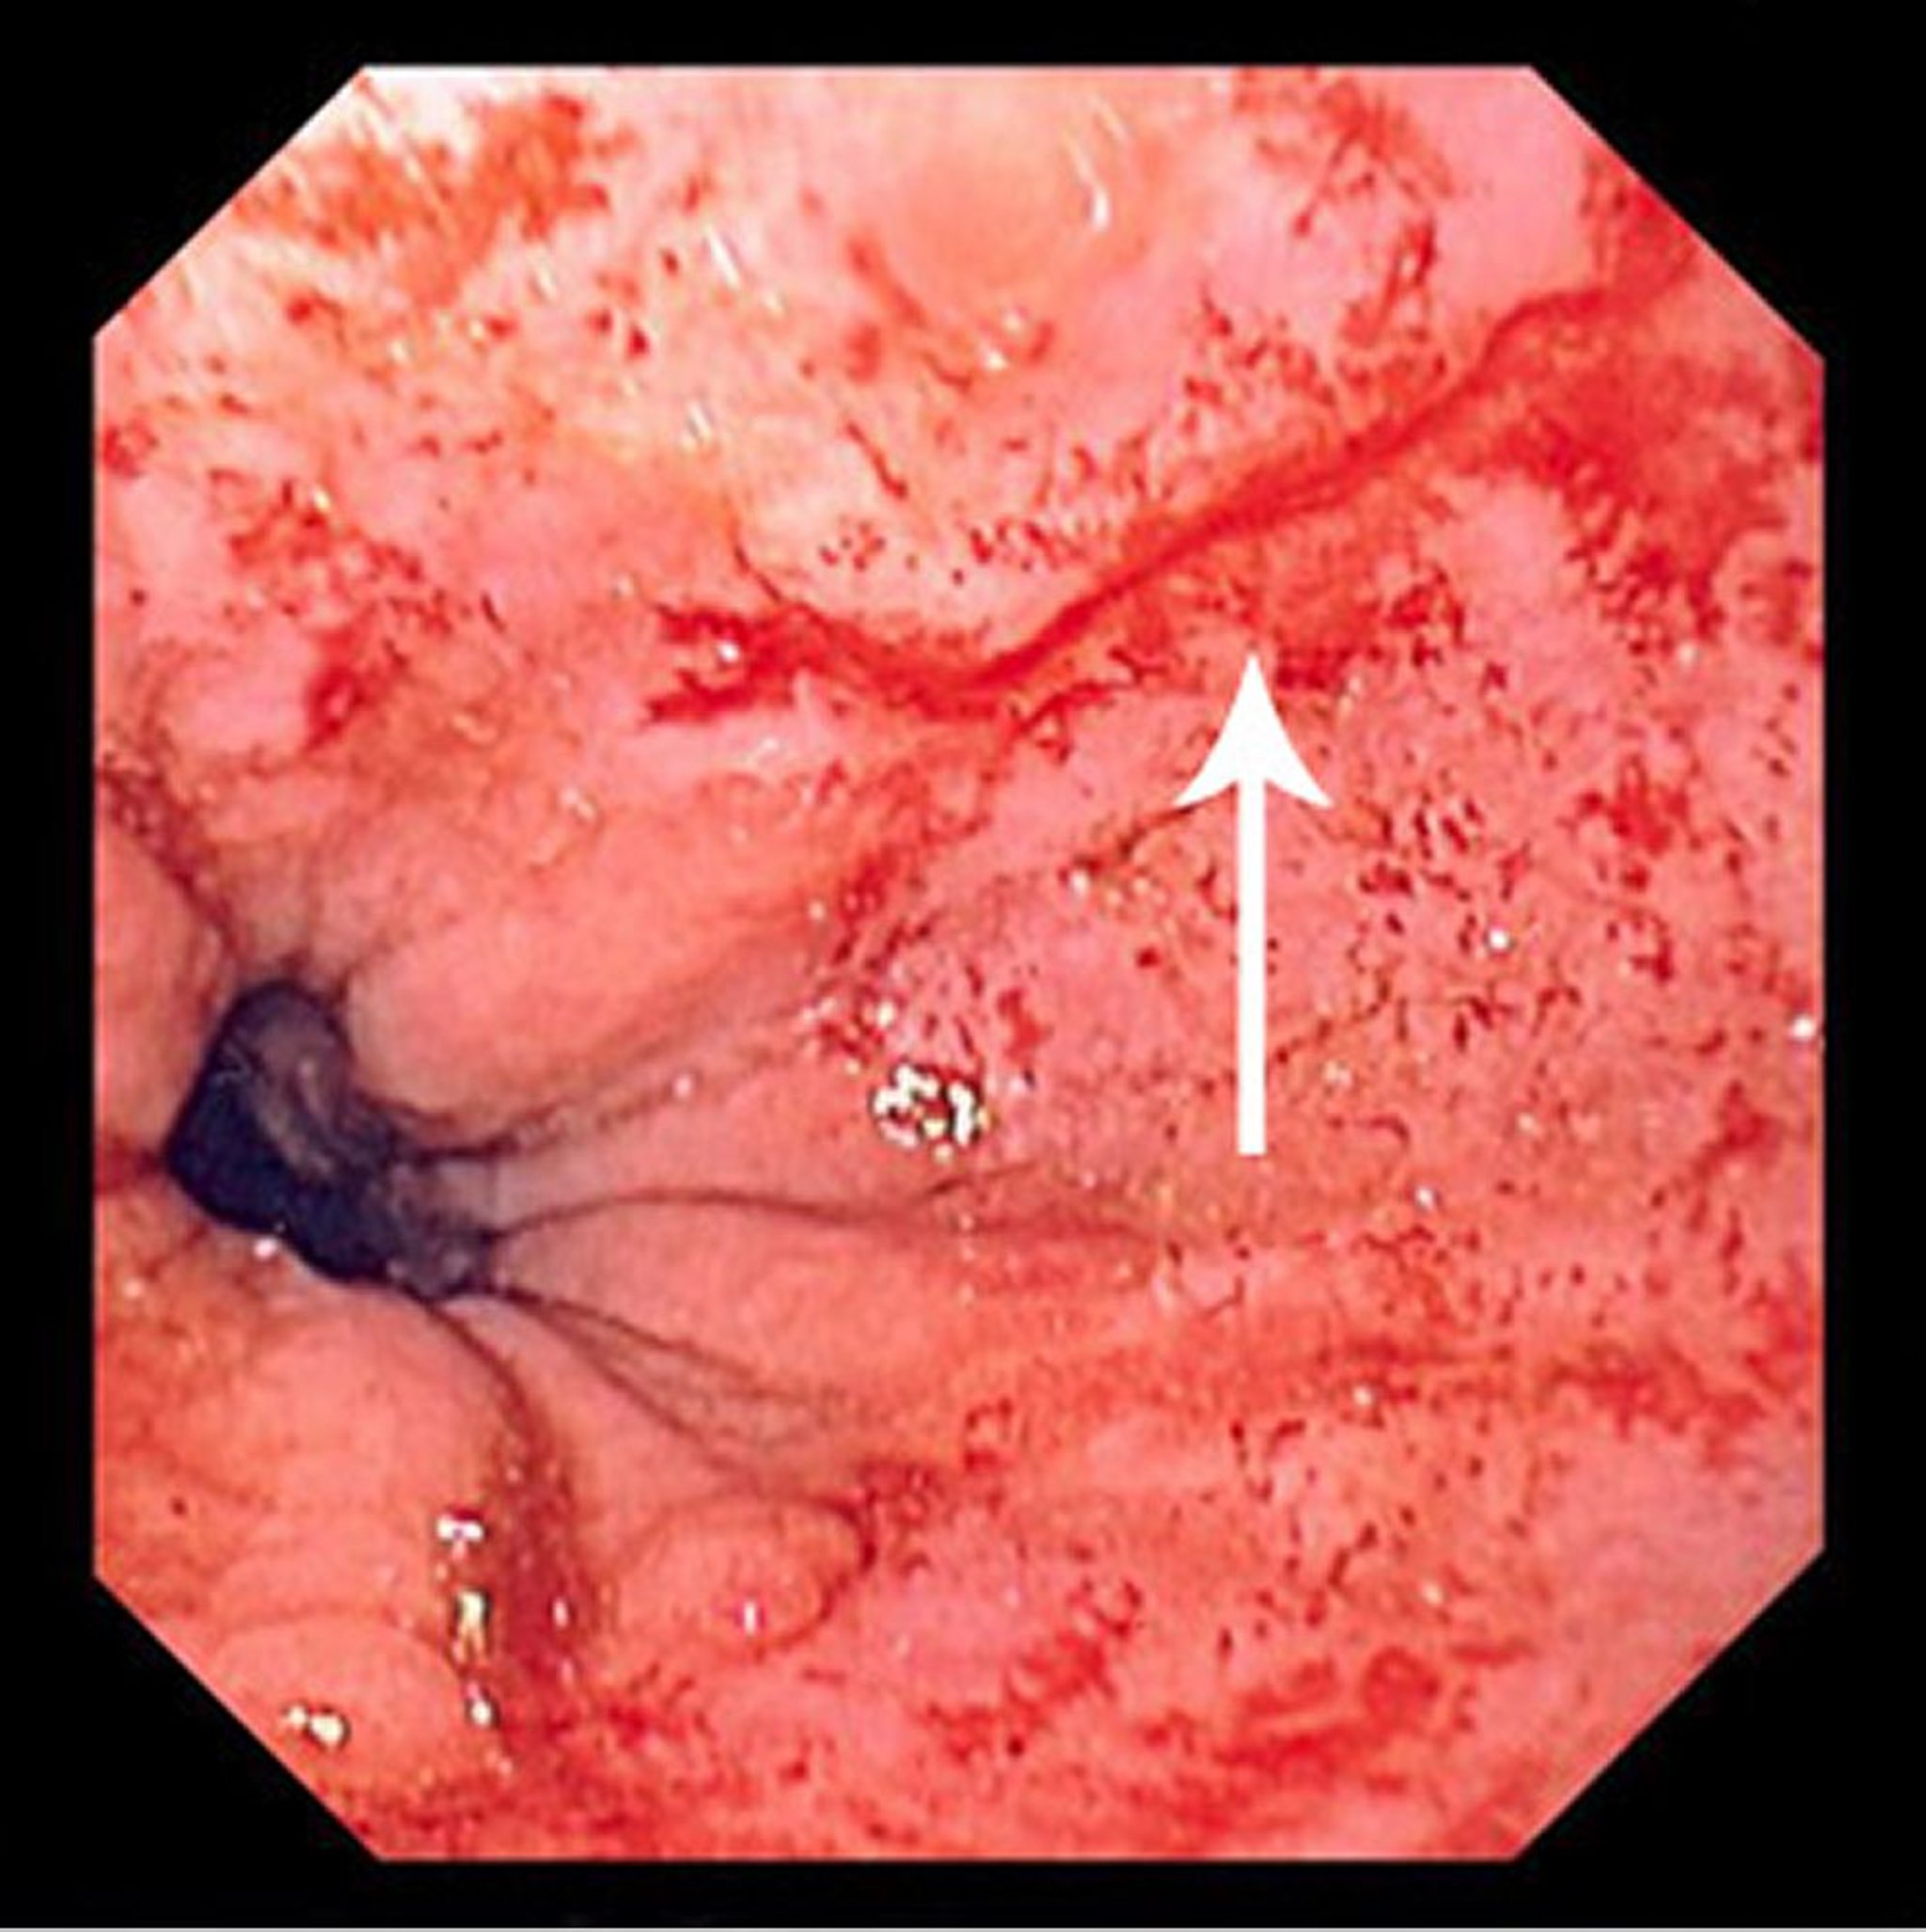

Синдром Мэллори-Вейса

На этом изображении показан тонкий линейный разрыв (отмеченный стрелкой), начинающийся чуть выше зоны перехода плоского эпителия пищевода в цилиндрический эпителий и простирающийся проксимально.

Image provided by David M. Martin, MD.